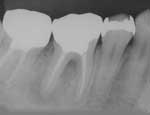

感染根管治療症例(3) 男性Oさま

治療前